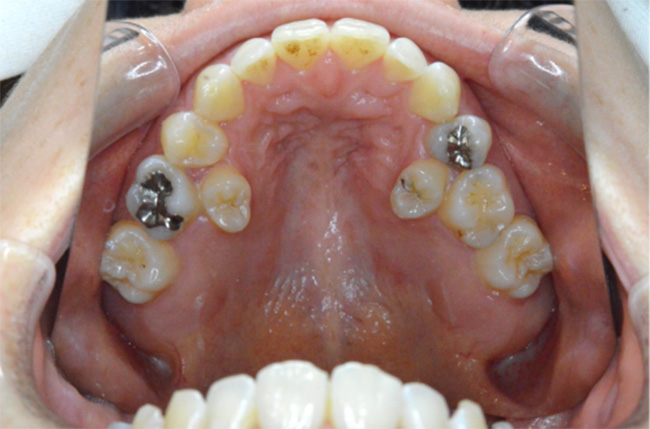

治療開始時

| 治療方法 | 上下顎小臼歯4本抜歯、ワイヤー矯正 |

| 治療内容 | 抜歯のスペースを使用して、上下前歯を後退させた |